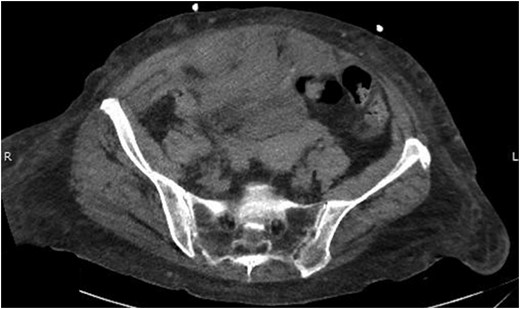

Her intra-abdominal bladder pressure (IAP) was noted to be 31 mm Hg (Grade IV intra-abdominal hypertension). The patient was emergently taken to the operating room (OR) for abdominal decompression. Necrotic rectus muscle was noted when the fascia was transected. Two liters of organized clot and blood was removed which had dissected into the retroperitoneal space bilaterally. After the damage control laparotomy, the patient was admitted to the surgical ICU with temporary abdominal wall closure achieved by application of Abthera™ ‘Vacuum Assisted Closure’ (KCI, San Antonio, TX, USA). Patient was taken back to the OR within 24 h for re-exploration and abdominal fascial closure. She recovered very well from her surgery with normalized bladder pressures and complete recovery of renal function. A repeat CT scan on postoperative Day 10 showed complete resolution of her rectus sheath and retroperitoneal hematomas (Fig. 3).

Abdominal CT scan showing complete resolution of rectus sheath and retroperitoneal hematomas.